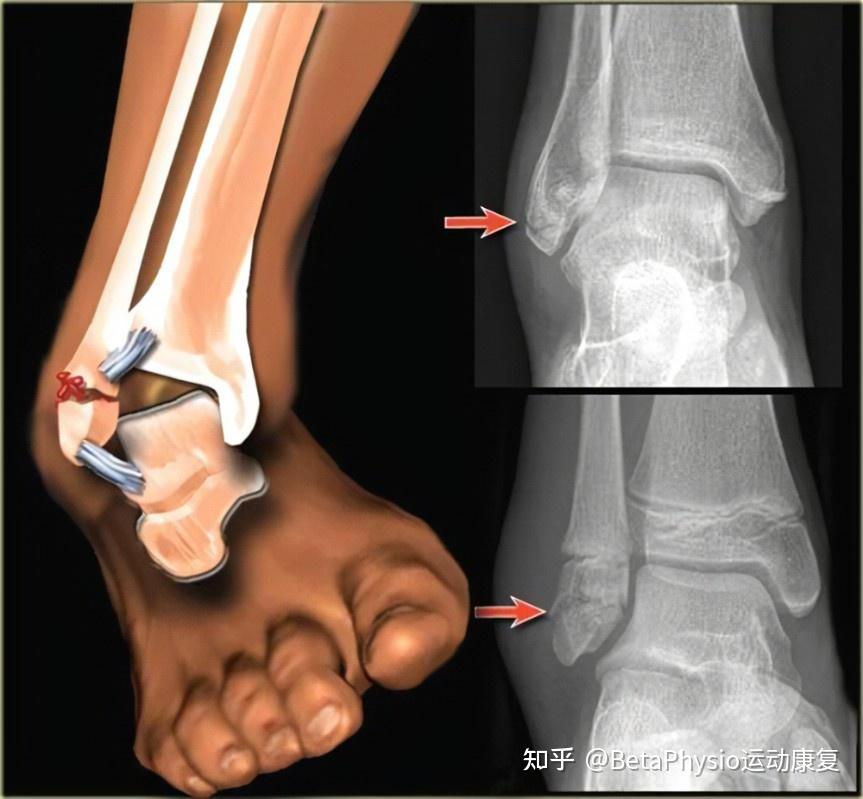

脚踝骨折brokenankle顺德倍他运动康复

图片尺寸863x799